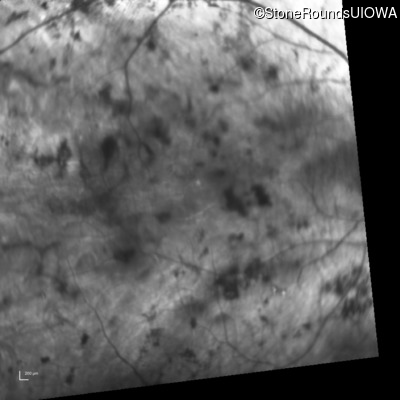

Infrared Fundus Photograph - Right - Light Perception

Exemplar

Infrared Fundus Photograph - Left - Light Perception